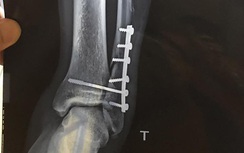

“Tôi bị tổn thương xương bánh chè và sừng sụn, phải nghỉ thi đấu ít nhất 3 tháng để tập phục hồi. Vì vậy, CLB không đăng ký tôi thi đấu ở lượt đi. Hy vọng tôi có thể trở lại vào giai đoạn lượt về”, Trần Thành chia sẻ.

Chấn thương đầu gối phải của anh xảy đến từ 2017 và liên tục tái phát. Mùa giải 2019, Trần Thành cũng gần như dành toàn bộ thời gian vật lộn với chấn thương.